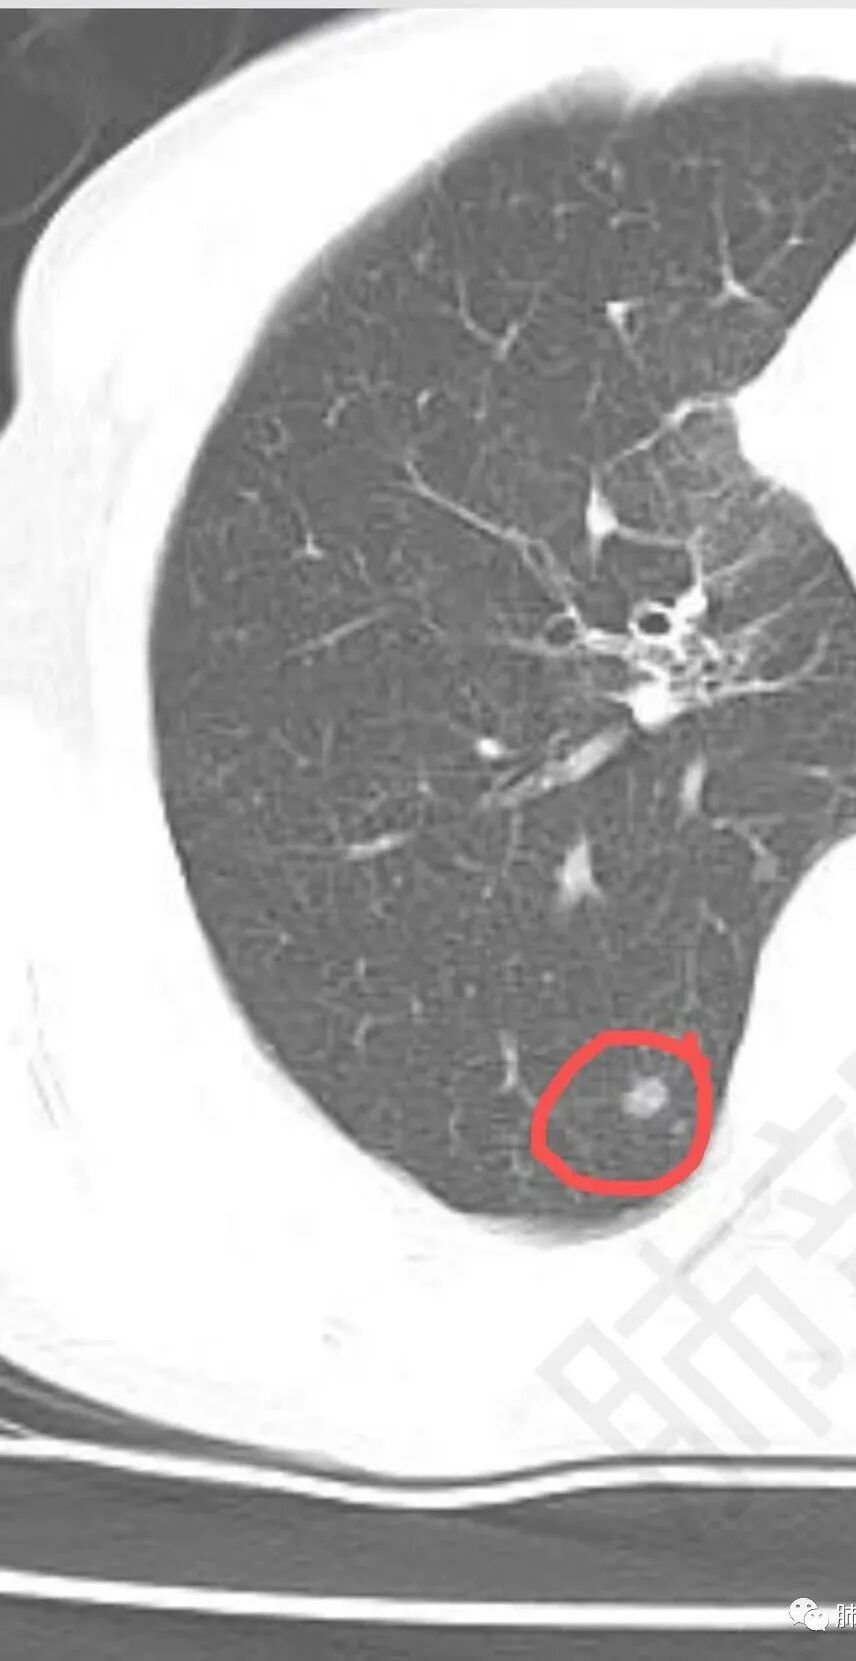

右下肺还有结节,不知道有没有意义?

右下叶背段有结节

南边 :

斑点